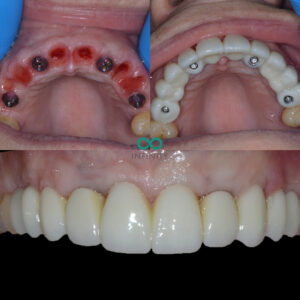

After a thorough clinical and CBCT scanning assessment we provided the patient with the option to have her failing teeth replaced with 4 dental implants and a permanent implant supported bridge. We also recommended a bone and gum graft to ensure that the damage done by her periodontal disease could be restored to build a stronger foundation for her dental implants.

During the treatment we provided our patient with fixed teeth from the very beginning of her treatment plan. She never spent any time without teeth. In fact, on the very same day that she had her teeth removed, we provided her with fixed dental implant supported teeth.

After the 6 months had passed, we carefully sculpted her gum line with all the volumous gum graft that had now worked and fully healed. The contours we had created were carefully designed to mimic her natural smile design that we planned using our digital smile desgin programmes. Following this careful gum sculpting process, we made a truly bespoke implant bridge that looked and felt as natural as is possible. The patient was delighted and we were especially proud of the fit between the gums and the implant teeth. That new gum line was healthy, natural and therefore very easy for the patient to clean and maintain daily with a normal electric toothbrush.

That is the thing with gum contouring – it enables us to provide natural teeth. Natural is important because it often means it will last longer and be more ‘natural’ to maintain too.